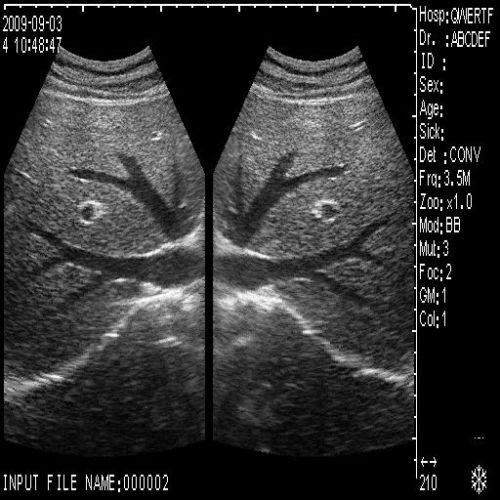

image: +3D High clear

Probe Function: 3.5MHZ convex, abdominal organs

The Diagnostic Ultrasound Scanner is an advanced medical device that uses high-frequency sound waves to create precise images of the body's internal structures. This technology plays an important role in diagnostics because it helps healthcare professionals identify issues such as abnormalities in organs and tissues, leading to early intervention. The incorporation of a Convex and Transvaginal Probe offers versatility, making it suitable for various examinations. Using this ultrasound scanner, doctors can provide better care and ensure patient satisfaction.

Enhanced Visualization with 3D Imaging

One of the standout features of the Diagnostic Ultrasound Scanner is its 3D imaging capability. This feature allows for comprehensive views of anatomical structures, which is critical for accurate diagnosis. Patients benefit from clearer images that assist in identifying conditions that may not be visible with traditional 2D scans. Therefore, the scanner enhances diagnostic confidence, helping practitioners make informed decisions regarding treatment plans. Additionally, the engaging 3D visuals can facilitate discussions with patients about their health.